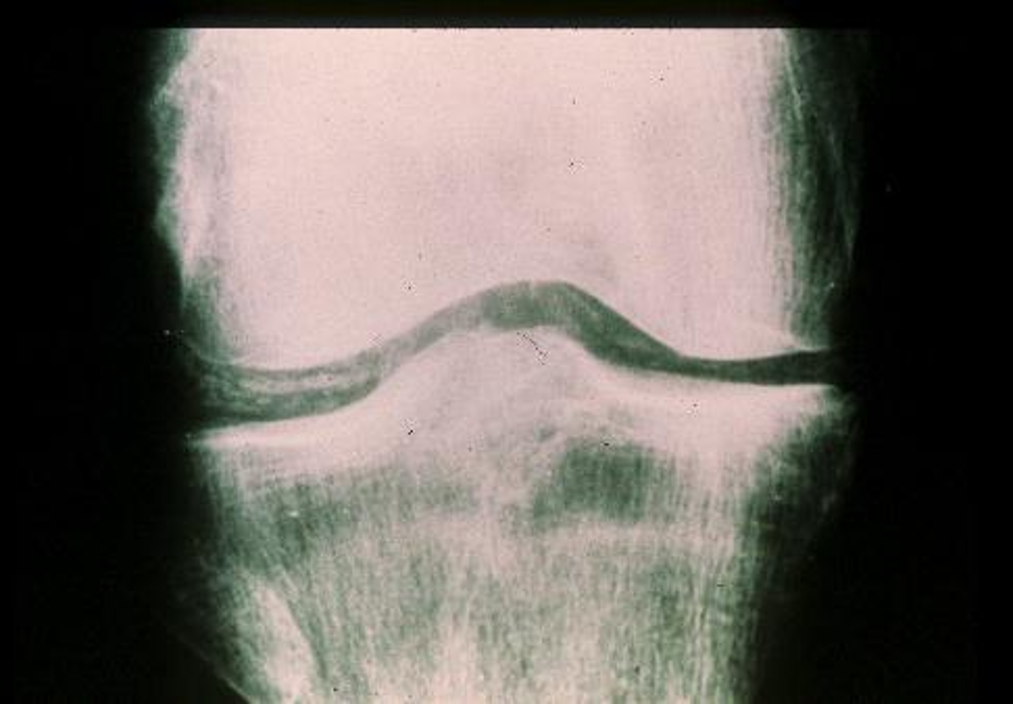

chondrocalcinosis

gout or arthritis

radiographic findings associated with OA

narrowed joint space, osteophytes, subarticular cysts